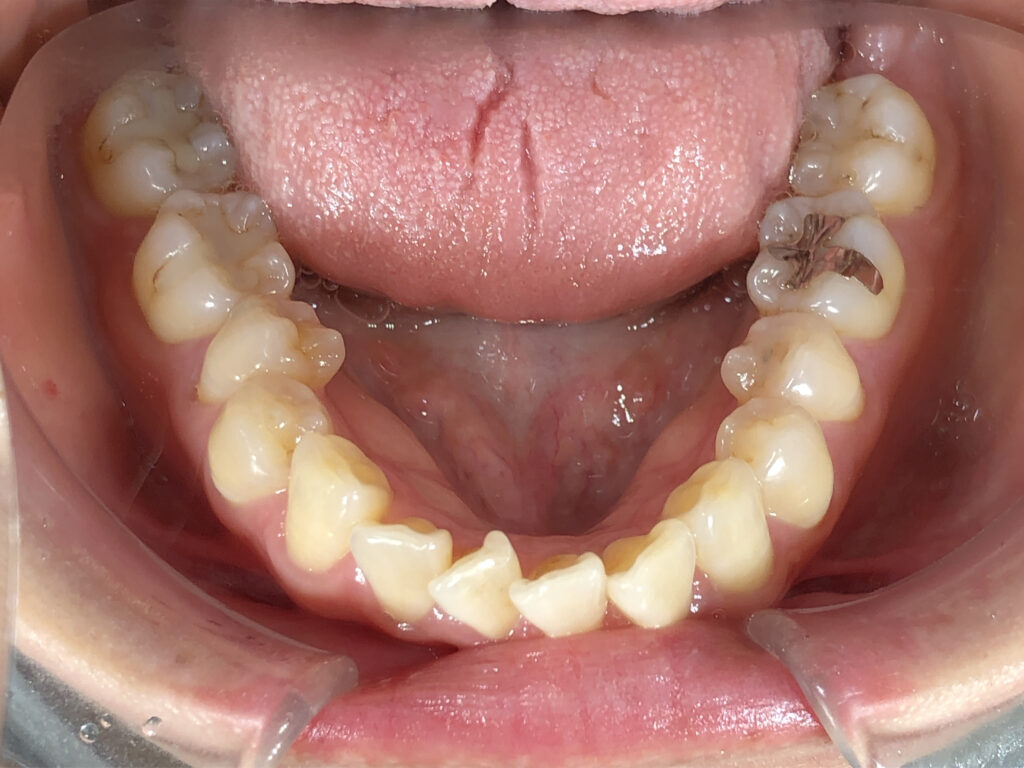

下顎

治療前

患者様は前歯の隙間と歯の向きを主訴として来院されました。前歯の隙間は審美面だけでなく、発音や食べ物の停滞にも影響しやすい状態でした。また、下顎前歯部に歯石が付きやすいことは、歯列不正により清掃不良部位が生じていることが一因と考えられました。 インビザライン矯正では、前歯の角度と位置を適切にコントロールし、隙間を閉じて調和のとれた歯列に整えました。同時に下顎前歯の叢生を改善することで、歯石の付着しやすい環境を改善し、将来的な歯周病リスクの低減にもつながる治療計画としました。下顎はもう少し改善可能と説明したところ、十分満足とのことで、治療終了としました。 |